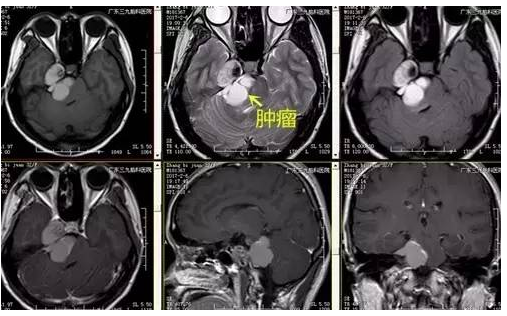

张女士,32岁,因右侧面部针刺样痛疼伴麻木持续2月余未有缓解,速来医院就诊,门诊CT提示右侧中后颅窝等密度影,收入住院治疗。入院后完善相关术前检查,术前DWI检查示右侧跨中后颅窝占位性病变呈低信号,术前磁共振示哑铃状病变,各序列以高信号为主高低混杂信号影,瘤体约4.5cm×3.7cm×3.3cm,完善检查后,行右侧中后颅窝占位性病变切除术,手术由神经一科主任张良主刀完成。术程顺利,术后患者恢复良好,未见并发症,术后MR提示肿瘤切除。